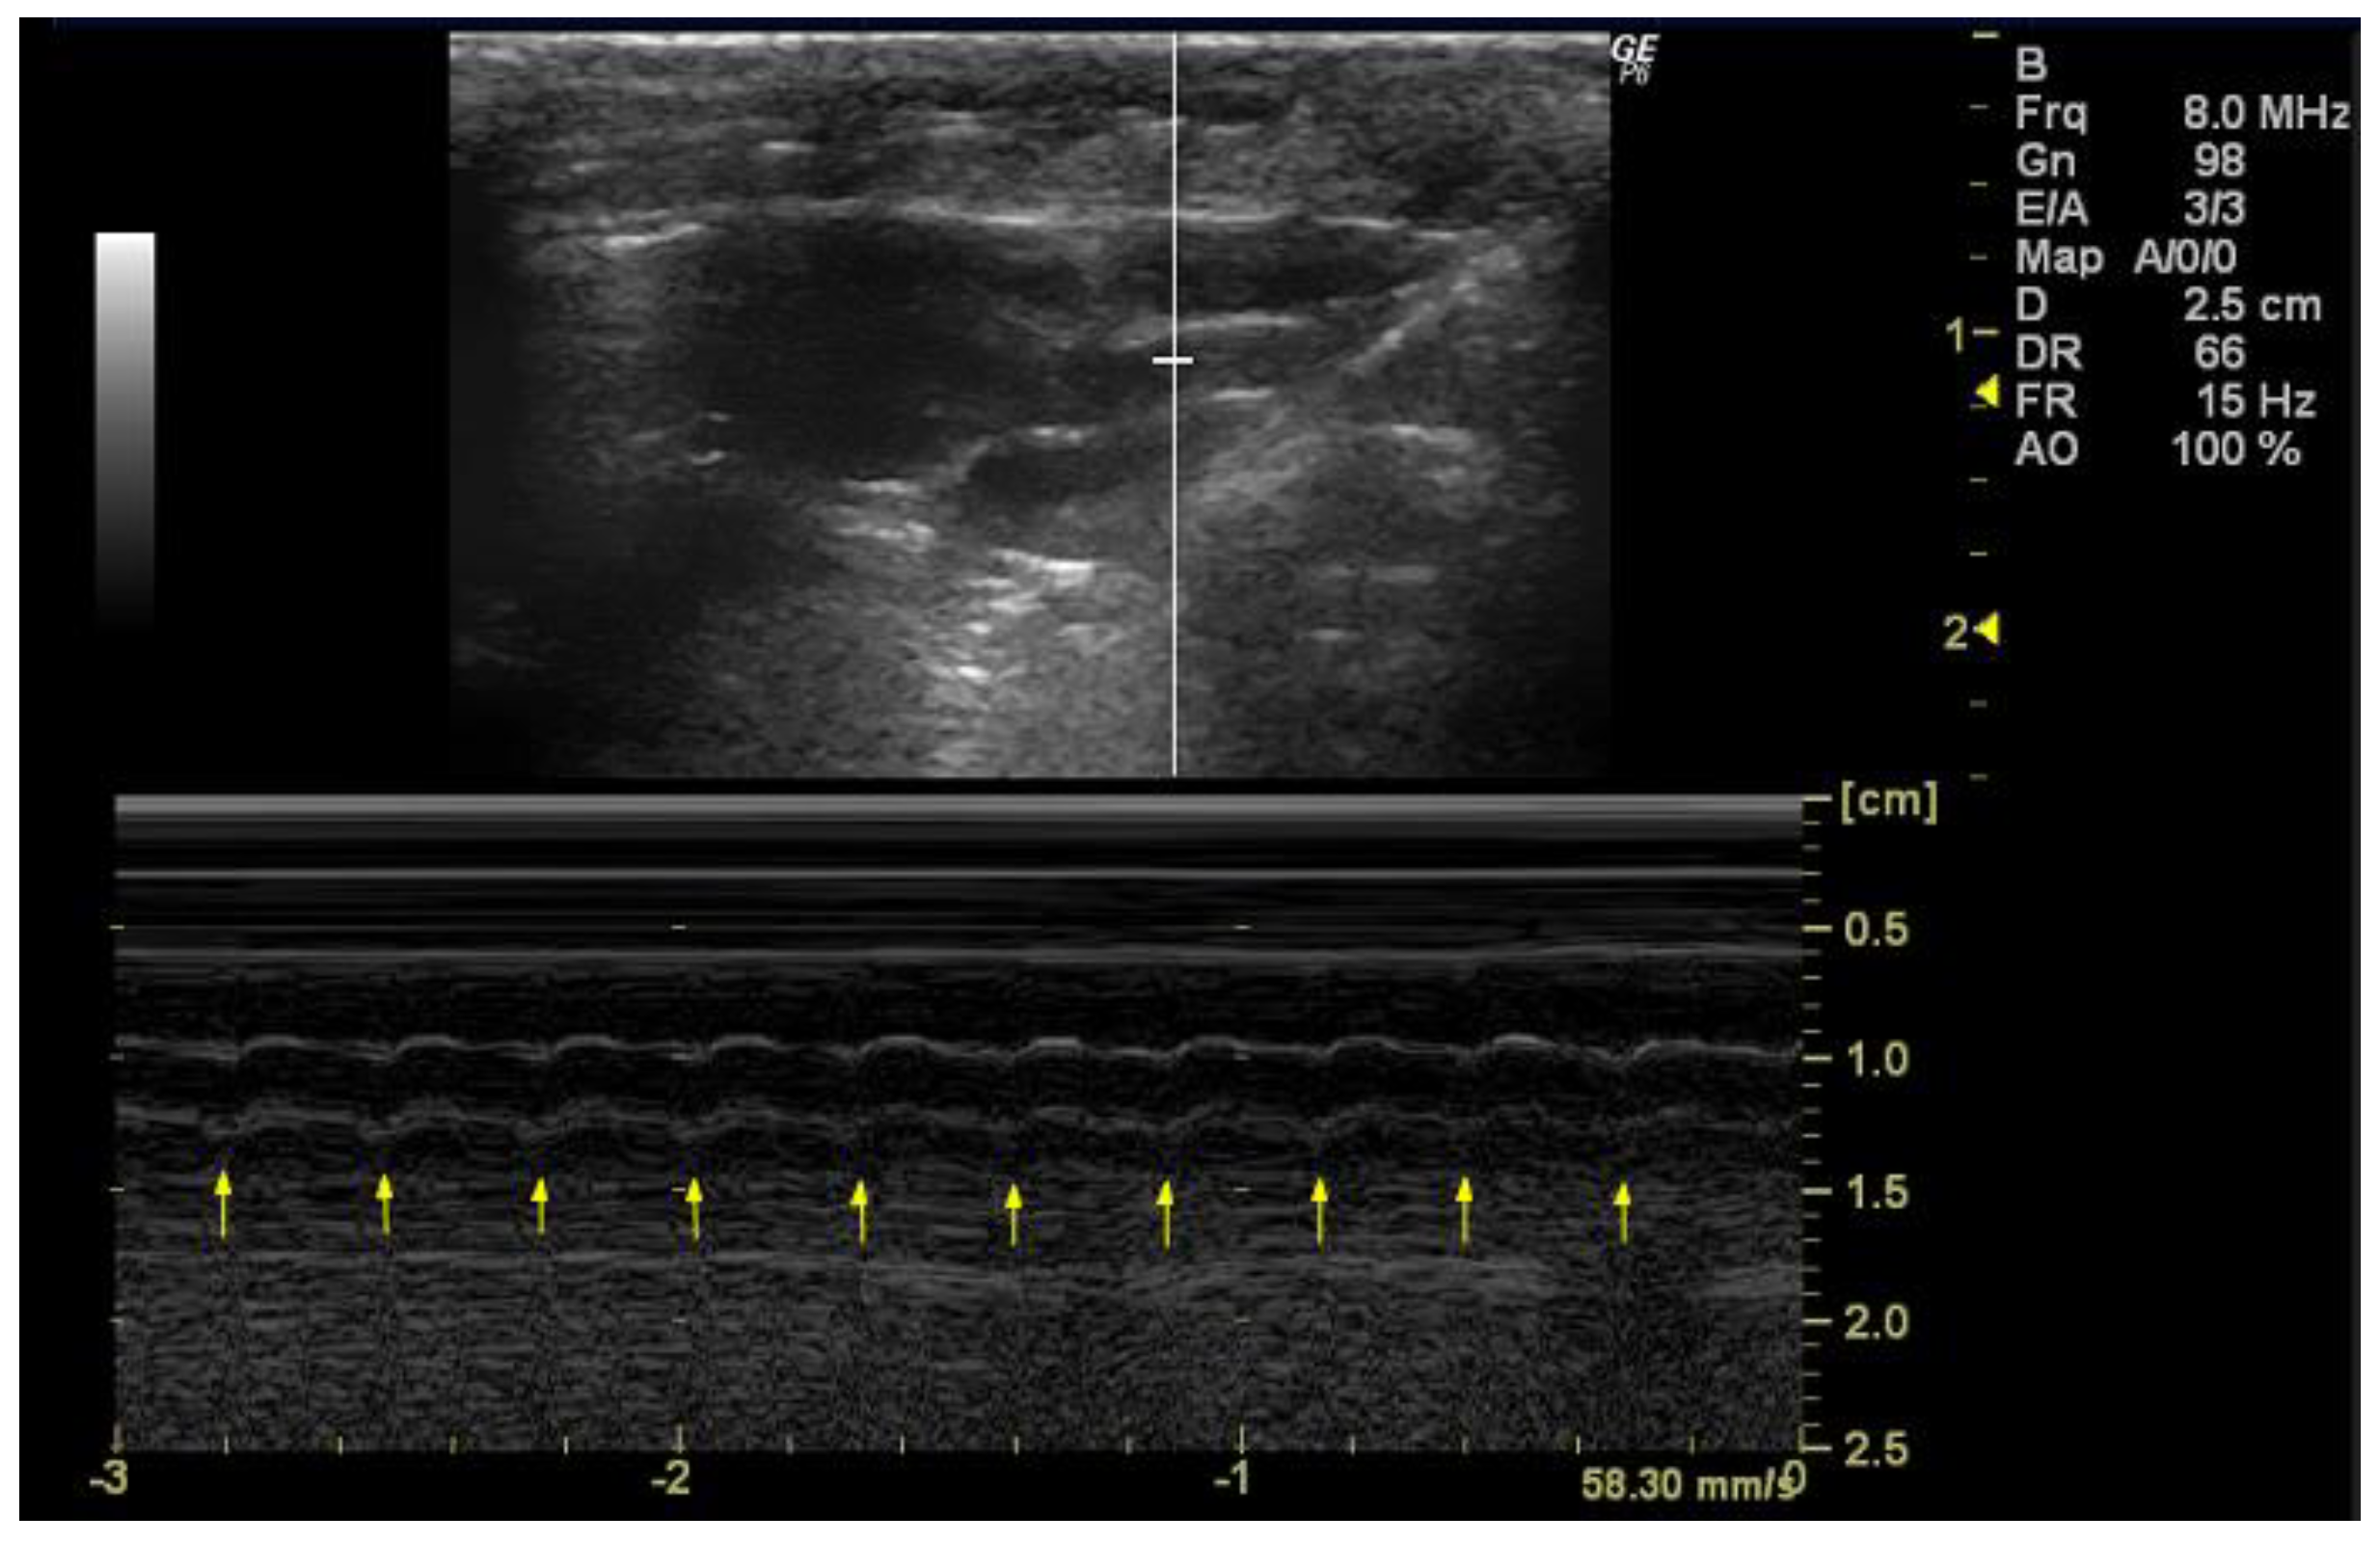

- How to measure HR